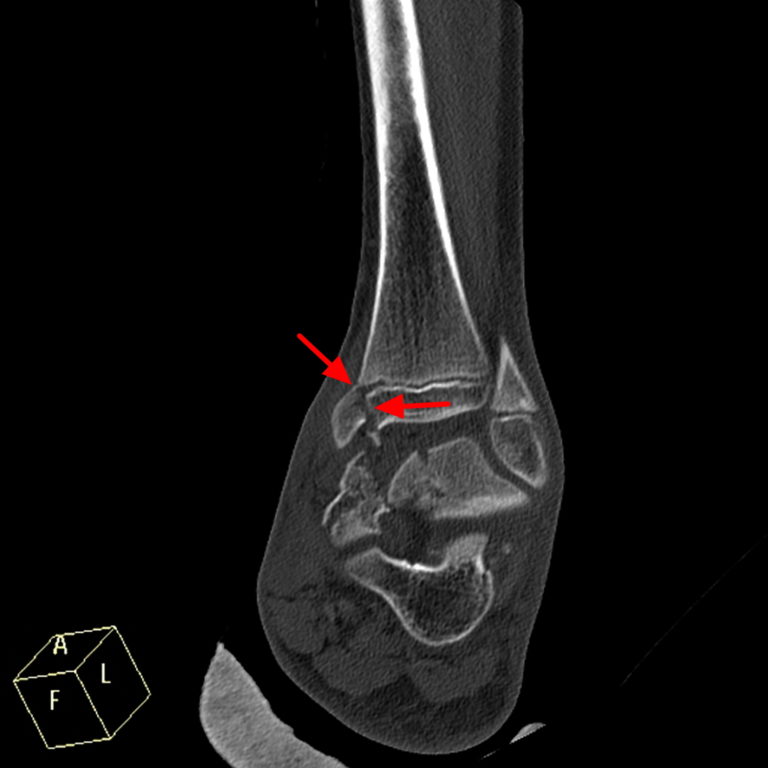

Growth plate fracture, Xray Stock Image F036/5535 Science Photo Growth Plate Fracture Cast Web most kids need to wear a cast for around a month after a growth plate fracture (usually four to six weeks). Web some growth plate fractures are treated with a cast or splint, but if the fracture is more severe, the broken pieces of bone are put. Without treatment, growth plate fractures. Growth plate fractures are an important presentation. Growth Plate Fracture Cast.

Growth plate fracture, Xray Stock Image F036/5536 Science Photo Growth Plate Fracture Cast Without treatment, growth plate fractures. But because they are still growing, a child's bones are. Web most kids need to wear a cast for around a month after a growth plate fracture (usually four to six weeks). Web some growth plate fractures are treated with a cast or splint, but if the fracture is more severe, the broken pieces of. Growth Plate Fracture Cast.

Growth plate fracture, Xray Stock Photo Alamy Growth Plate Fracture Cast Growth plate fractures are an important presentation in children and teenagers, and need urgent. What is a growth plate fracture? Web a growth plate fracture happens when an accident or overuse causes a break in the growth plate tissue. It might take longer if they had a more severe type of. Web most kids need to wear a cast for. Growth Plate Fracture Cast.

Growth plate fracture, Xray Stock Image F036/5307 Science Photo Growth Plate Fracture Cast Web a growth plate fracture happens when an accident or overuse causes a break in the growth plate tissue. Web images (1) lab test (0) sidebars (0) tables (0) videos (0) locating growth plates. But because they are still growing, a child's bones are. Web most kids need to wear a cast for around a month after a growth plate. Growth Plate Fracture Cast.